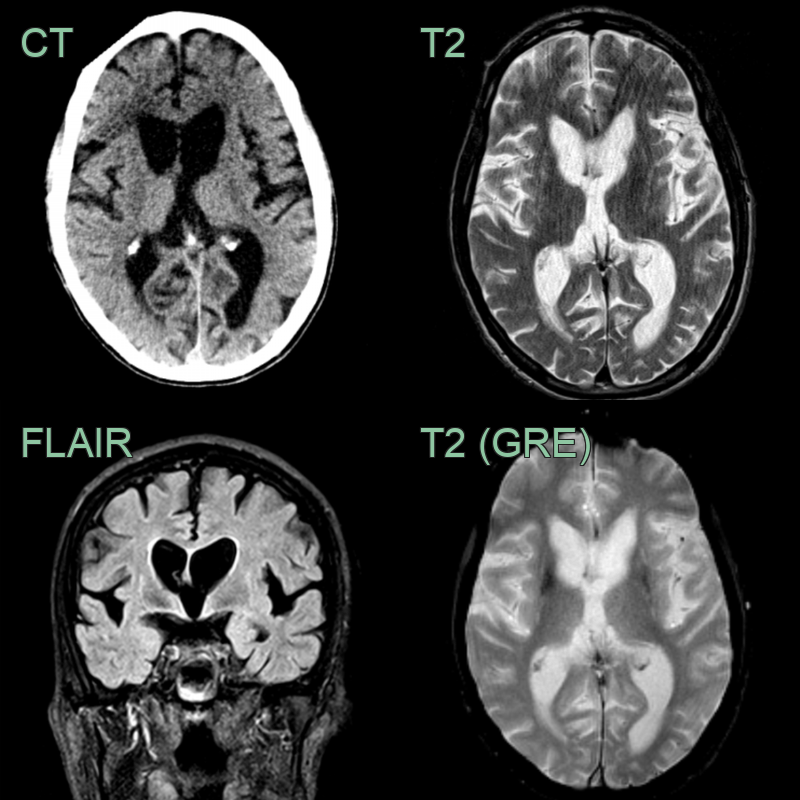

Huntingdon's disease is characterized by atrophy of the caudate nuclei resulting in a 'boxed' appearance of the frontal horns o f the lateral ventricles in the coronal plane.